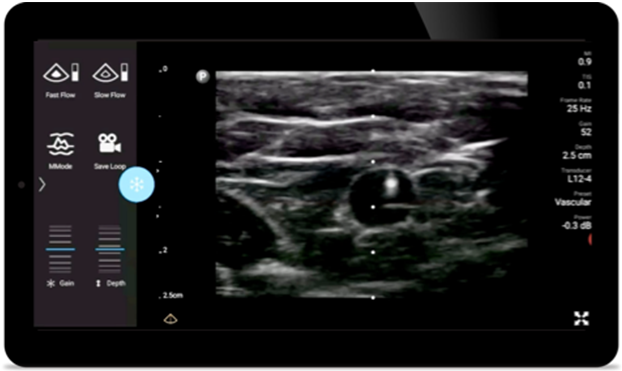

Reduzca las complicaciones en procedimientos guiados por aguja

El ultrasonido portátil Lumify para anestesiología le ayuda a visualizar claramente la definición de los bordes con la colocación de la aguja, los nervios circundantes, los vasos sanguíneos y los planos fasciales.

Transductor de matriz lineal de banda ancha Lumify L12-4